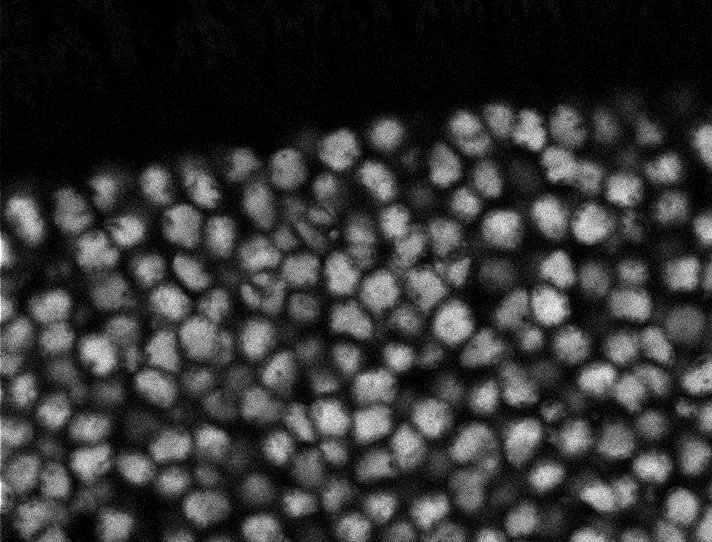

Actin

Nuclei

Nuclei - Bis

Tubulin